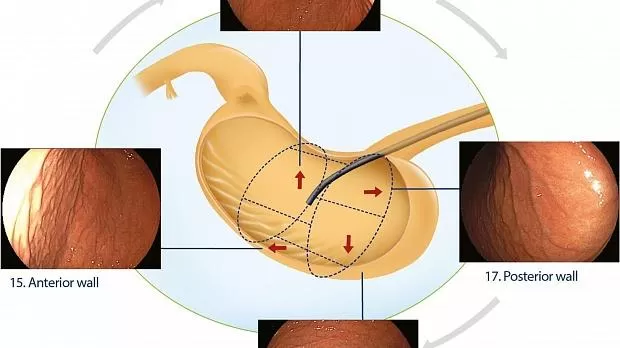

Нижняя треть

После оттягивания назад дистальная треть исследуется по часовой стрелке с четырьмя изображениями крупным планом с прицелом, ориентированным по оси желудка, где большая кривизна расположена в нижней части эндоскопического поля: передняя стенка, включая переднюю часть режущего края. angularis, область 11; меньшая кривизна, где выпуск воздуха позволяет его захват, более вертикально ориентированный, область 12; задняя стенка, включая заднюю часть угловой вырезки, область 13; и большая кривизна, где часто видна эпителиальная переходная зона, область 14 (рис. 5 ).